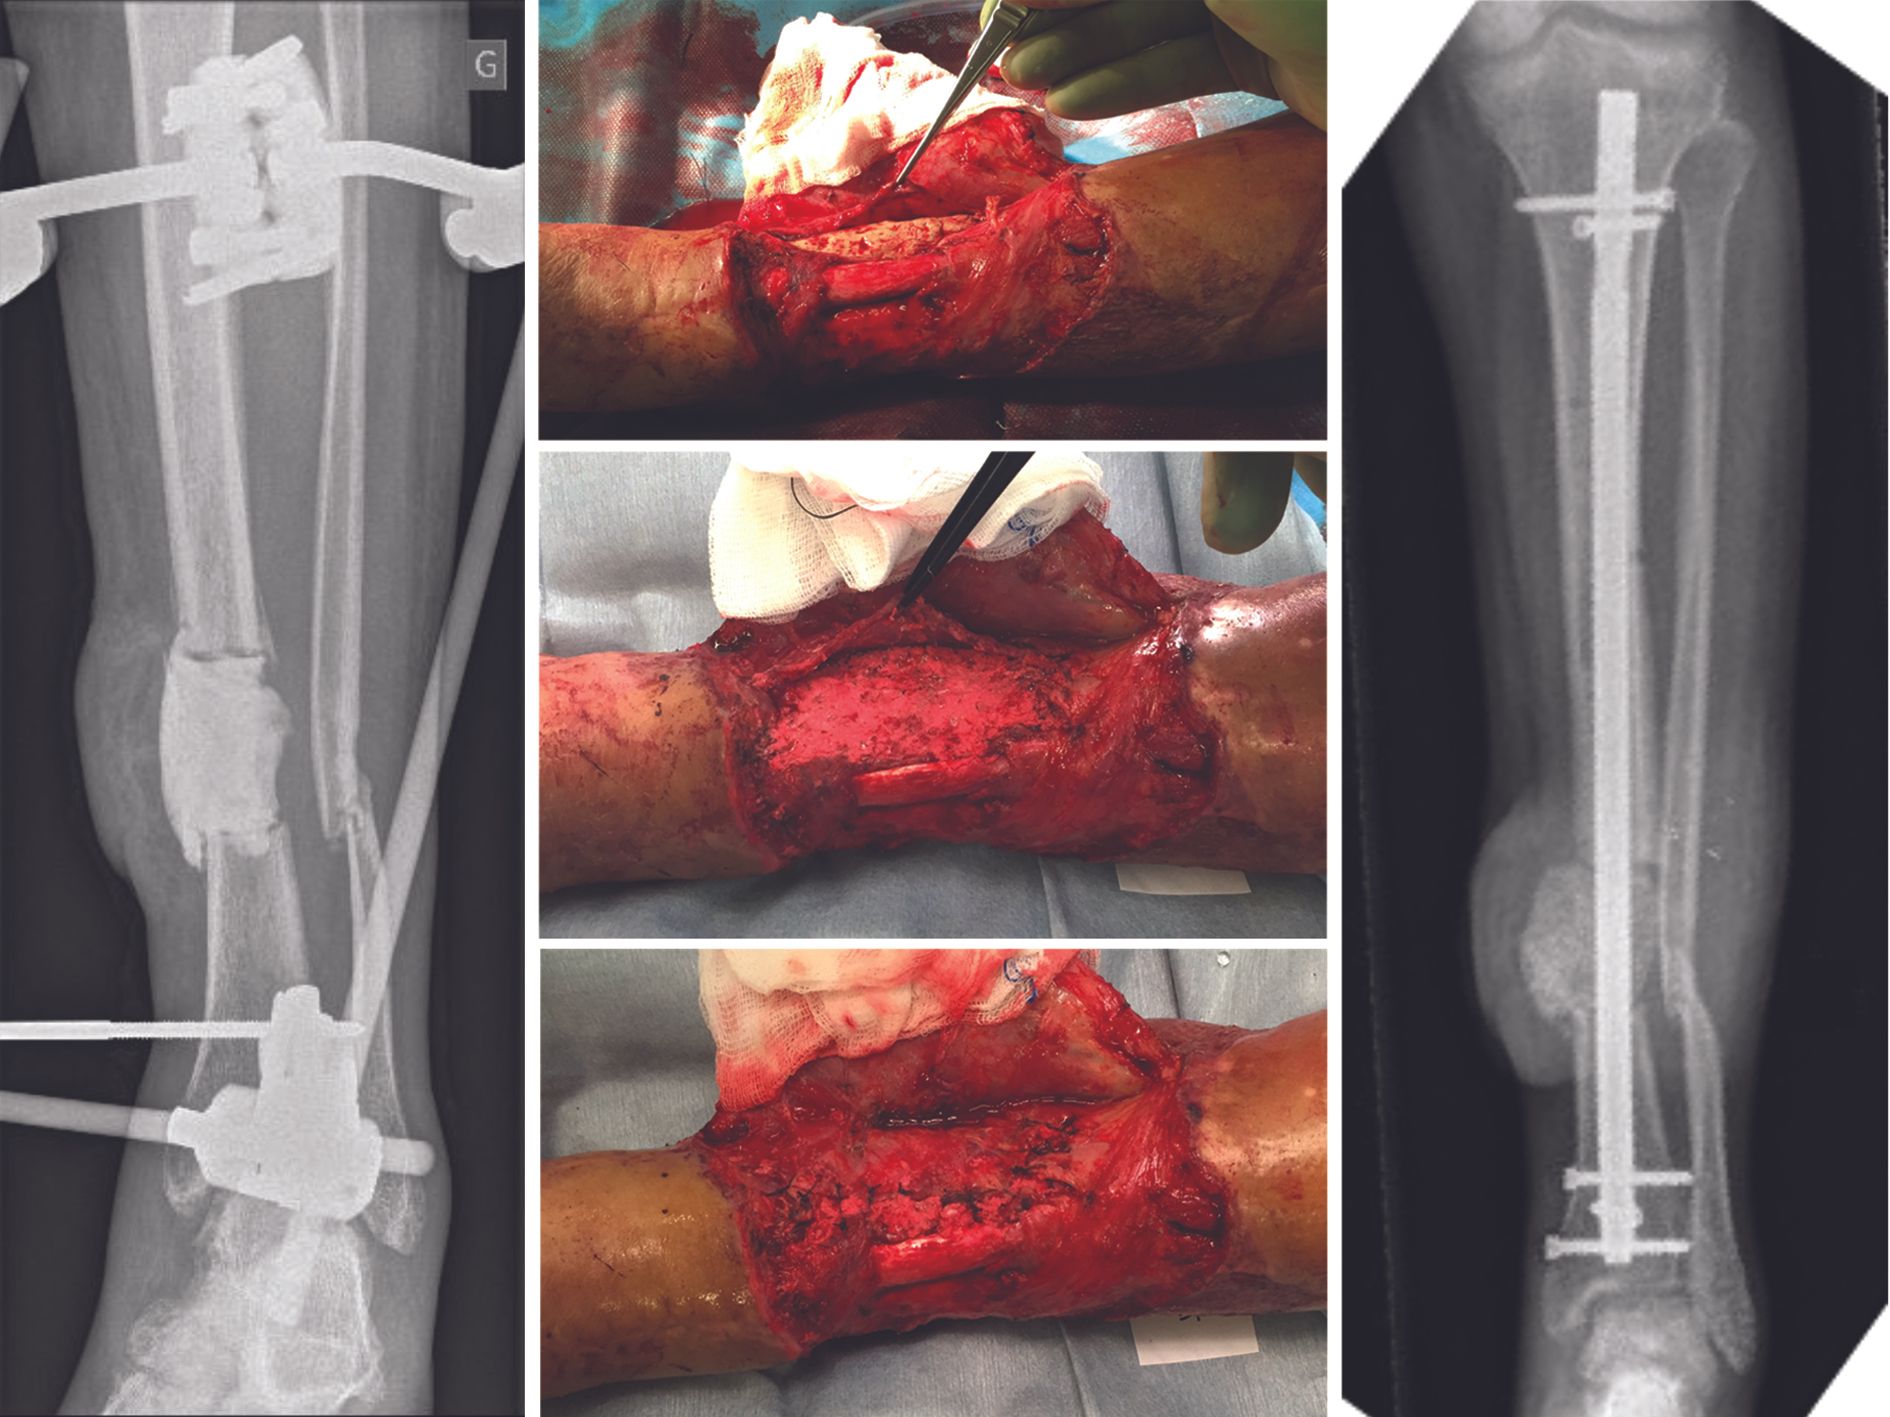

The therapeutic strategy is to perform a resection of the pseudarthrosis until healthy bone is encountered (Fig. 6 A), insert an antibiotic bone cement spacer (Fig. 6 B) and then combine these local antibiotics with intravenous antibiotic therapy. In a second stage, which should be performed at least 6 weeks later, the surgeon replaces the spacer with a bone graft using the Masquelet technique or an intercalary prosthesis (Fig. 6 C). Intravenous antibiotic therapy should continue for several weeks post-surgery, depending on the type of infection.

Mechanically, pseudarthrosis results in bone loss of varying degrees, depending on the extent of the infected bone which has to be removed. The bone loss must be compensated by a bone graft and fixed by an appropriate osteosynthesis device or by an intercalary prosthesis. Mechanical reconstruction must be performed once the infection is under control. Masquelet two-stage reconstruction, described above, is the most widely used surgical technique for infected pseudarthrosis with substantial bone defect after debridement.

Intravenous antibiotic therapy alone is insufficient to treat the infection. The pseudarthrosis consists of poorly vascularized, non-vascularized bone or sequestrate, where intravenous antibiotic therapy alone is ineffective. Patients with implanted osteosynthesis devices may also fail to respond to antibiotic therapy due to biofilm formation. The osteosynthesis device must be replaced during revision surgery.